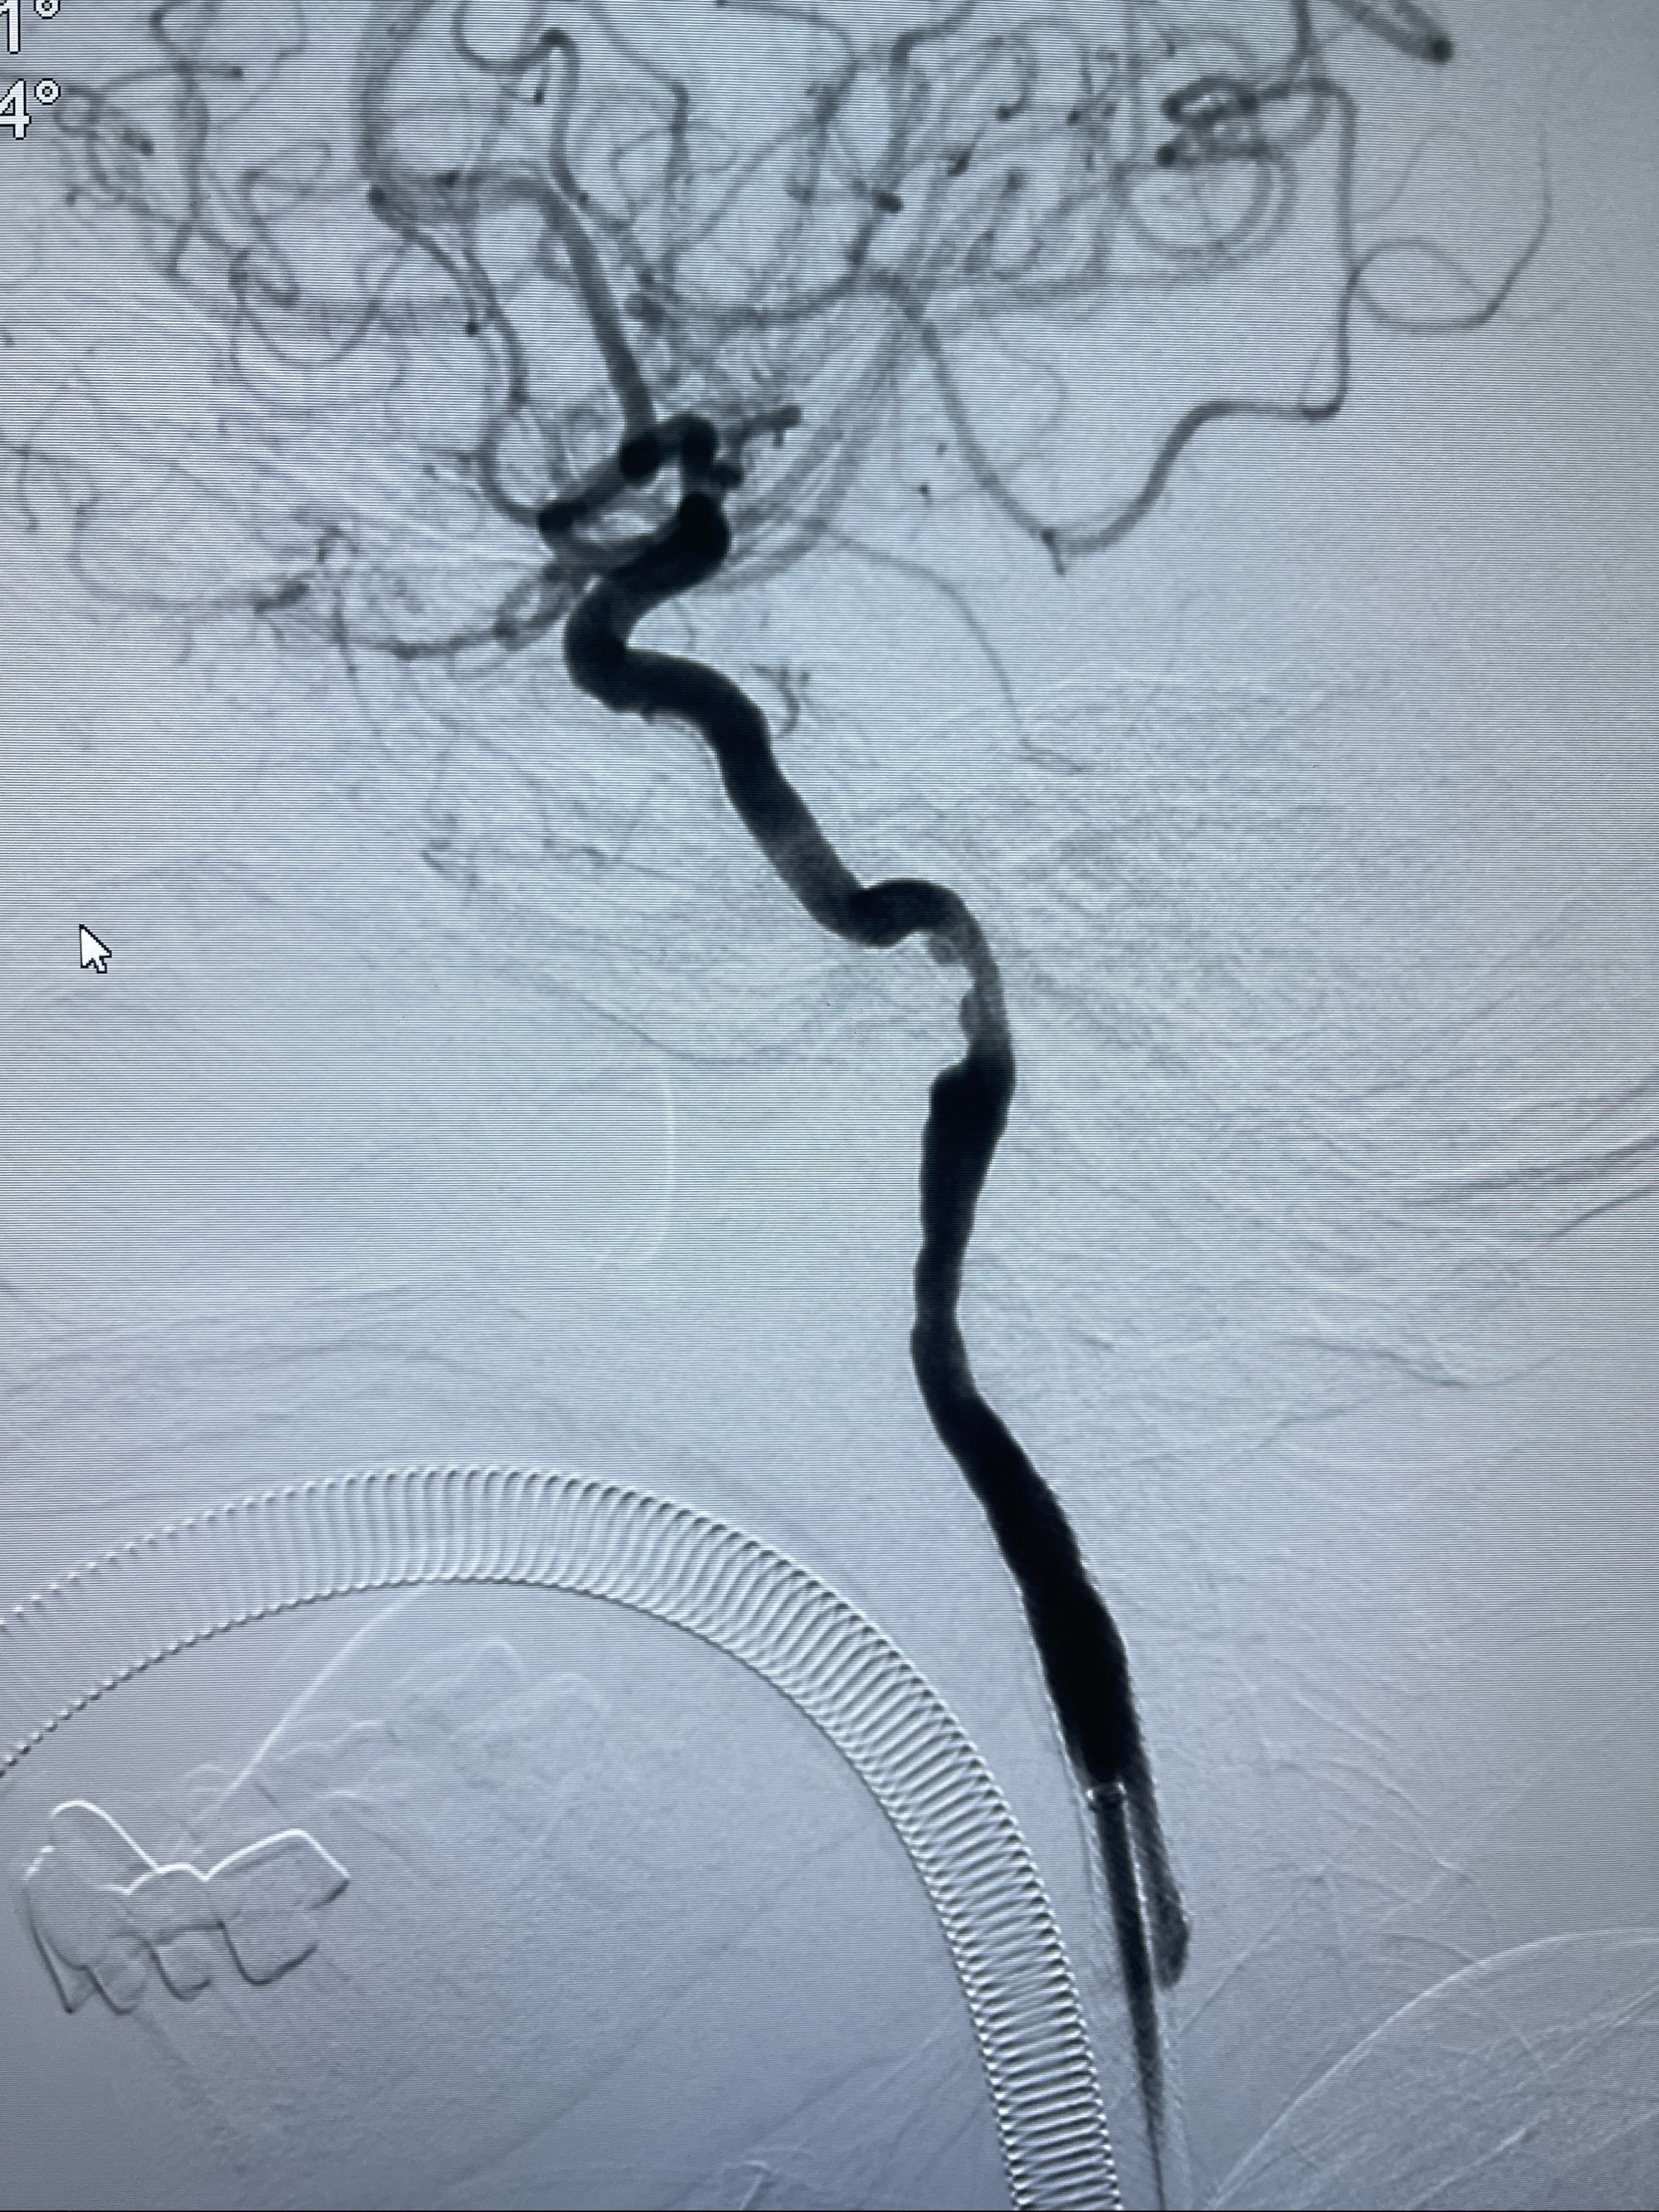

2023-07-10DSA:右侧颈内动脉岩骨段夹层伴中偏重度狭窄改变,左侧颈总动脉闭塞、右侧颈外动脉由右侧肋颈干甲颈干吻合代偿

箭头所示为颈内动脉岩骨段重度狭窄,结合MRI,考虑为肿瘤侵犯右侧颈内动脉

箭头以近至支架段管腔不规则狭窄

088NeuroMAX100cm长鞘在125cmMPA及黑泥鳅导丝引导下超选择性插入右侧颈内动脉支架内

经导引导管造影显示支架远端颈内动脉不规则狭窄伴局部充盈缺损,同时行全身肝素化5ml